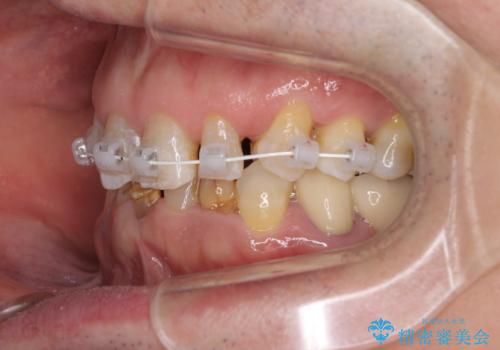

- 乳歯や矮小歯が多くある前歯部の審美障害が気にして来院された患者様です。

上顎の矮小歯は隙間が多く、歯軸の傾斜も大きかったため、部分矯正により補綴治療前に歯の位置を整えることとしました。

下顎の乳歯は支台歯として機能することは困難と思われたので、事前に抜歯をし、上顎の矯正治療終了のタイミングに合わせて、セラミックブリッジにて補綴治療することとしました。

前歯部はディープバイトという、上顎前歯が下顎前歯に深く覆い被さる咬合であったので、理想的には全顎矯正が必要となりますが、今回は患者希望により前歯部のみの部分矯正で対応しました。そのため下顎犬歯の神経を取り除くことになってしまったのは心残りであります。